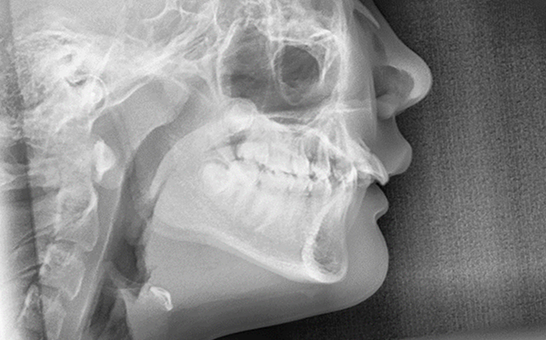

디지털 기반의 시뮬레이션 진단 과정을 통해 치아의 배열, 턱 관절 상태,

교합 상태를 정밀히 분석 후 교정 치료 계획을 수립하여 복잡한 케이스,

어려운 고난도 케이스도 전문적인 교정 치료가 가능합니다.